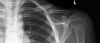

영상 검사

Clavicle AP, Oblique, 10º cephalic tilt view에서 확진이 가능합니다.

쇄골 내측 끝 부위에서의 골절이나 탈구는 드물며 골절이 의심되더라도 X-ray에서는 안 보이므로 CT가 필요합니다.

X-ray : 쇄골 골절(Clavicle shaft fracture)